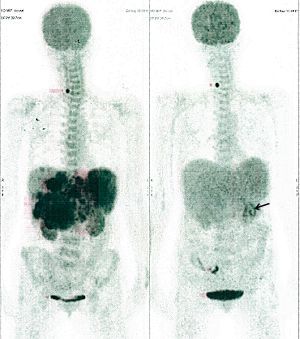

CASE NO: 29 (OVARIAN CANCER)

A 40+ women has recurrent ovarian cancer in the lower abdomen, resistant to chemotherapy. After a few treatment, most of the cancer went into remission with only a small bit left. Treatment is continuing.